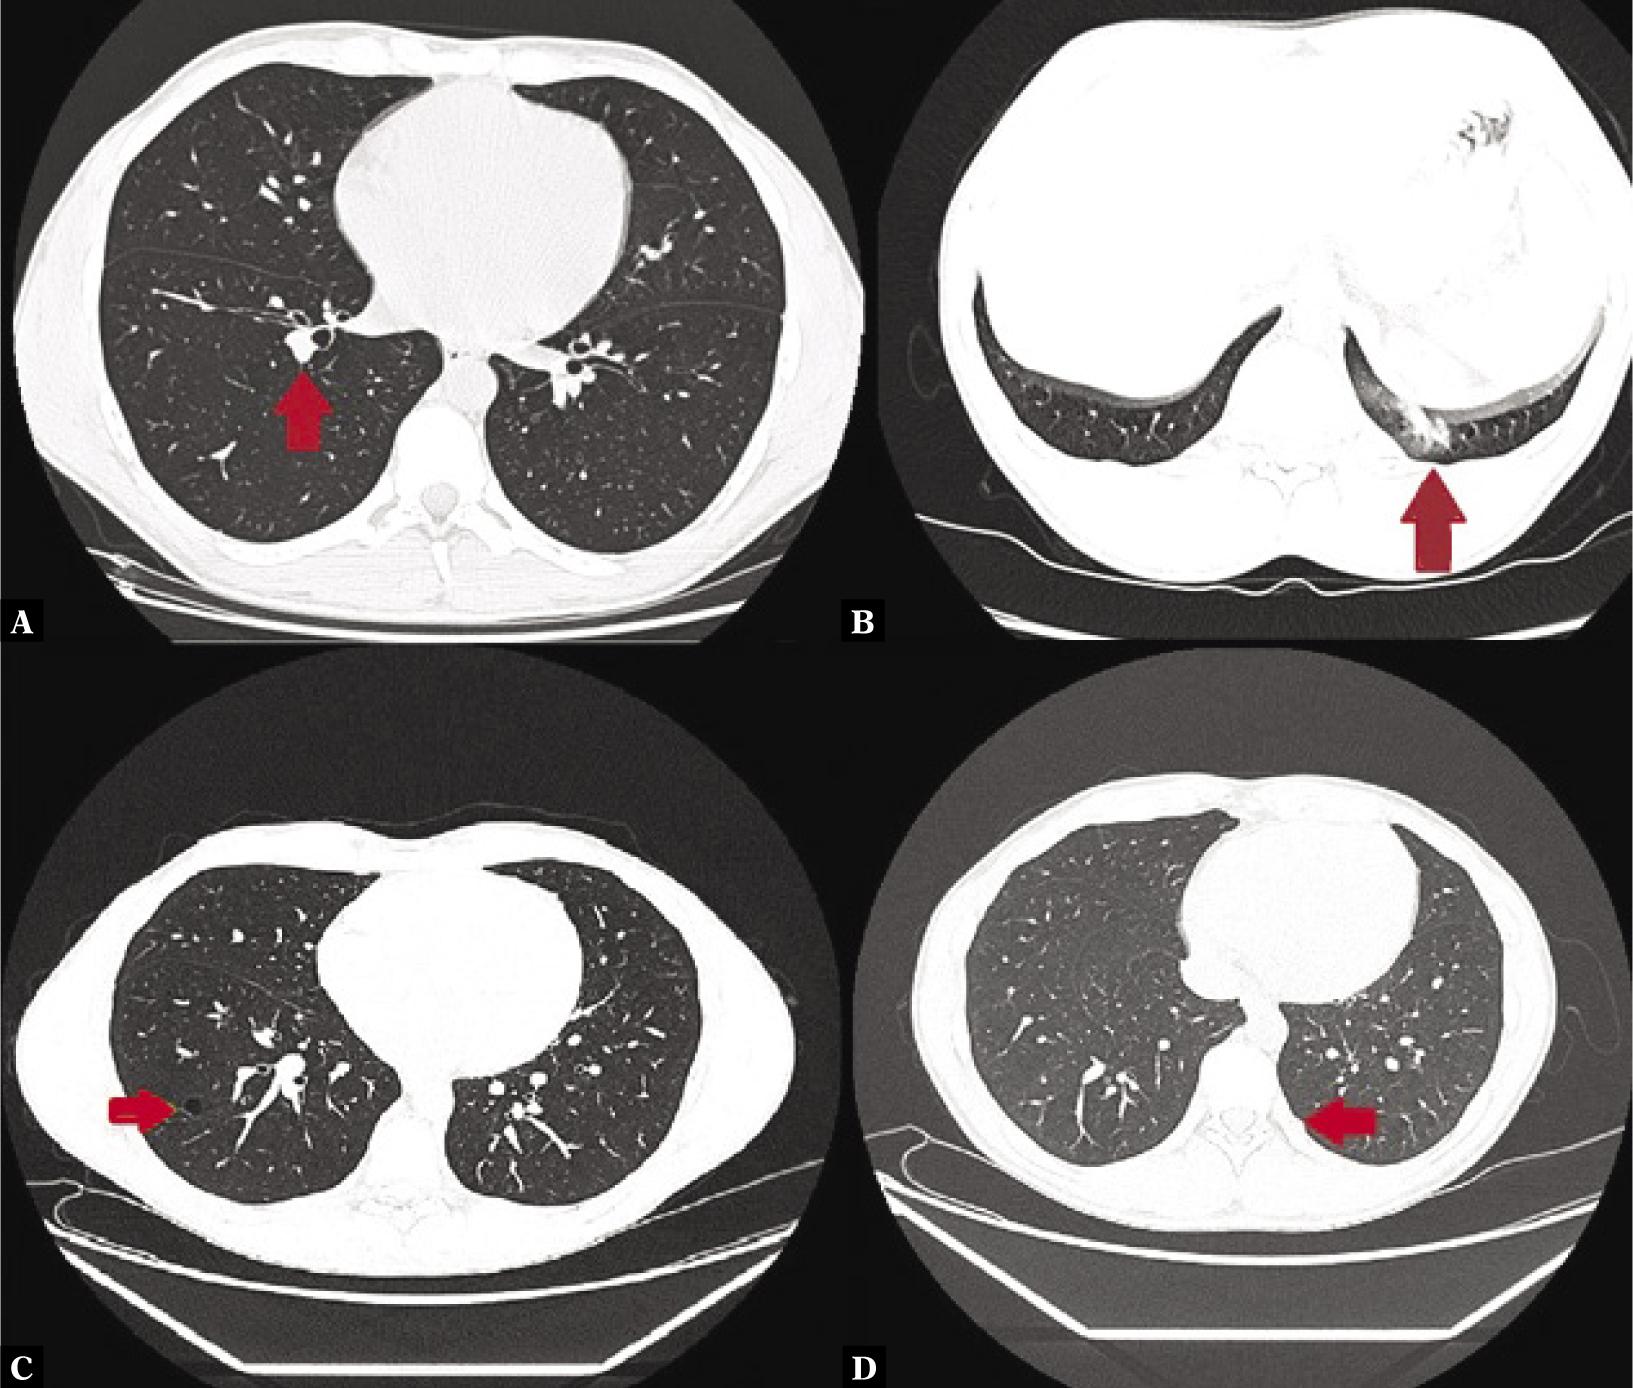

Fig. 4.

Pattern of changes visible on HRCT

| Normal parenchyma | 363 (83.6%) | 49 (87.5%) | 200 (84.0%) | 103 (81.7%) | 11 (78.6%) |

| Minor changes (adhesions, small scars and fibrotic changes, small consolidations) | 38 (8.6%) | 2 (3.6%) | 19 (4.3%) | 15 (11.9%) | 2 (14.3%) |

| Major changes (ground glass opacifications, big consolidations) | 10 (2.3%) | 3 (5.4%) | 2 (0.8%) | 3 (2.4%) | 2 (14.3%) |

| Non-specific changes (nodules, small tumors) | 25 (5.8%) | 3 (5.4%) | 15 (7.6%) | 6 (4.8%) | 1 (7.1%) |